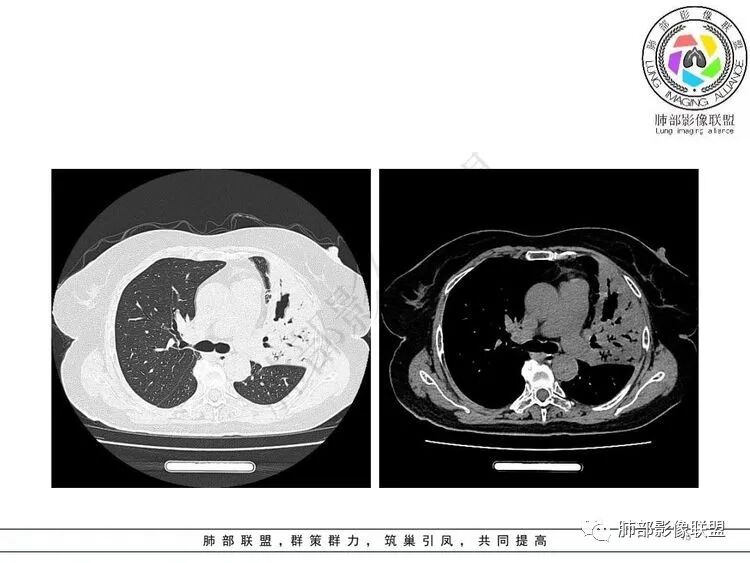

壁连续软骨破坏不明显可见不规则空洞,内壁光滑、腔内干净,远端支气管显示清楚病灶收缩明显左下叶见多发边界清楚结节、树芽征

3.左肺上叶较大范围实性密度区,密度偏高不均,支气管穿行且轻度扩张,可见无壁不规则空洞(未能显示外壁),未显示液平或腔内结节。

4.左肺下叶多发结节影及条索影,密度不均,边界较清楚,可见树芽征。

5.纵隔见轻度增大淋巴结,较密实。

1.左肺上叶较大范围实性密度区,支气管未见阻塞,无壁空洞,整体比较“干”,加之纵隔左移,比较符合病程较长的结核性病变。

左肺下叶多发结节影、条索影、树芽征等具有相当明显的提示意义—符合继发性肺结核。